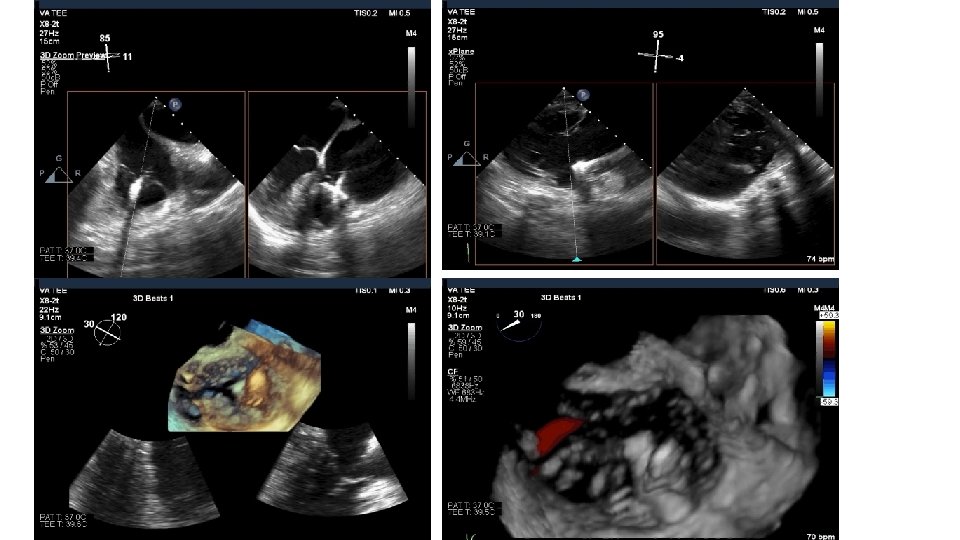

Tricuspid Valve (TV) Imaging • TV imaging is challenging • Three TV leaflets (anterior, septal and posterior) are thin and membranous Huitin et al. Archives of Cardiovascular Diseases Volume 109, Issue 1, January 2016, Pages 67 -80

• TV assessment • severity of TR • Mechanism of • mode of leaflet coaptation, • degree of tricuspid annulus enlargement and tenting • TAPSE • 3 D-TEE • Cardiac CT • cardiac MRI

80 yo male with mild dementia referred for evaluation of Progressive dyspnea >1 year Exam: venous distention, TR murmur, no RV lift Creat 2. 2 Transthoracic Echo: Isolated severe TR. IVC 3. 3 cm. RA is dilated RV normal function. Dilated annulus (4. 2 cm)-presumed mechanism of TR. TEE, right heart catheterization RAP 16, and coronary angiography: non obstr CAD What do you do next? Medical management, Refer to CV surgery , other options